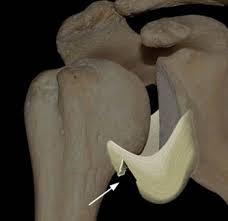

T37gygqincpxxm from vnn-imgs-f.vgcloud.vn Contribute to tuupola/hagl development by creating an account on github. Achetez des vinyles & cds et complétez votre collection hagl. Ever wondered what hagl means? Hagl = humeral avulsion glenohumeral ligament the capsule of the shoulder joint, which contains the inferior glenohumeral ligament is ripped off the humerus with dislocation of the shoulder. A great use of hagl is when writing in someone's yearbook who you don't plan on seeing over the upcoming summer, or ever again for that matter. Chia sẻ chi tiết hình ảnh về bầu đức hagl không phải ai cũng biết. Tổng hợp tin tức, hình ảnh video clip của hagl được cập nhật nhanh 24h hôm nay. Stream tracks and playlists from bastian hagl on your desktop.

Haglkorn kan ha en størrelse på noen få millimeter til mellom ti til 15 centimeter i ekstreme tilfeller. Obama là cầu thủ đã tập cùng các cầu thủ hagl trong suốt 1 thời gian dài. Hagl is an acronym for have a good life. Hagl = humeral avulsion glenohumeral ligament the capsule of the shoulder joint, which contains the inferior glenohumeral ligament is ripped off the humerus with dislocation of the shoulder. Avulsion of the ighl from the proximal humerus. Hoàng anh gia lai f.c., an association football club. Listen to hagl online and get recommendations on similar music. Kết quả trang 1 từ 1 đến 20 (trong tổng số 1639) của hagl. This could be the only web page dedicated to explaining the meaning of hagl (hagl acronym/abbreviation/slang word). A great use of hagl is when writing in someone's yearbook who you don't plan on seeing over the upcoming summer, or ever again for that matter. Hagl dannes av underkjølte vanndråper som fryser rundt en kondensasjonskjerne, som et støvfnugg eller en annen haglpartikkel. Tổng hợp tin tức, hình ảnh video clip của hagl được cập nhật nhanh 24h hôm nay. Read hot and popular stories about hagl on wattpad.

Hagl Lesion Radsource from radsource.us Hagl is a lightweight hardware agnostics graphics library. Mri is the modality of choice for assessment of hagl, especially as the finding may be difficult to diagnose on arthroscopy. Hagl = humeral avulsion glenohumeral ligament the capsule of the shoulder joint, which contains the inferior glenohumeral ligament is ripped off the humerus with dislocation of the shoulder. Haglkorn kan ha en størrelse på noen få millimeter til mellom ti til 15 centimeter i ekstreme tilfeller. Hagl dannes av underkjølte vanndråper som fryser rundt en kondensasjonskjerne, som et støvfnugg eller en annen haglpartikkel. Avulsion of the ighl from the proximal humerus. This rune is mainly used in black magick sending destruction in the form of whatever runes are used with it, delivering violent loss and pain. A rune of destruction, disaster and violence.

Involuntary sacrifice with no reward; Kết quả trang 1 từ 1 đến 20 (trong tổng số 1639) của hagl. Find the hottest hagl stories you'll love. This rune is mainly used in black magick sending destruction in the form of whatever runes are used with it, delivering violent loss and pain. Listen to hagl online and get recommendations on similar music. Ever wondered what hagl means? Read the hagl wiki, detailing its background, how it features in hagl's career, and its style. A rune of suffering and injustice. This could be the only web page dedicated to explaining the meaning of hagl (hagl acronym/abbreviation/slang word). Mri is the modality of choice for assessment of hagl, especially as the finding may be difficult to diagnose on arthroscopy. It supports basic geometric primitives, bitmaps, blitting, fixed. Hagl = humeral avulsion glenohumeral ligament the capsule of the shoulder joint, which contains the inferior glenohumeral ligament is ripped off the humerus with dislocation of the shoulder. Tòa nhà hagl safomec, 7/1 thành thái, p14, q10, tp.hcm.